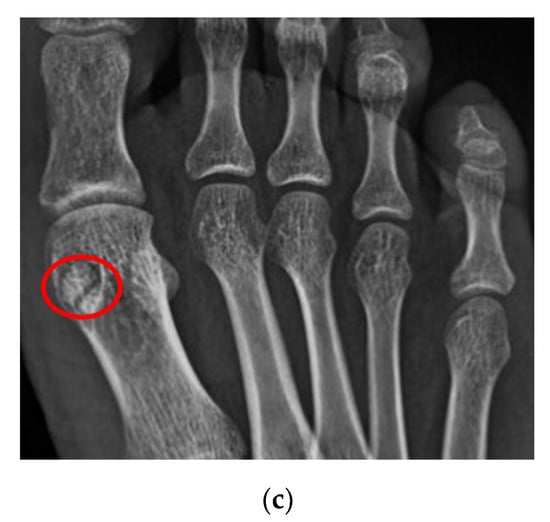

4.1.2. Sesamoiditis

| Sesamoiditis | / | blurred sesamoid bone cortex, with or without cortical disruption and surrounding soft tissue edema |